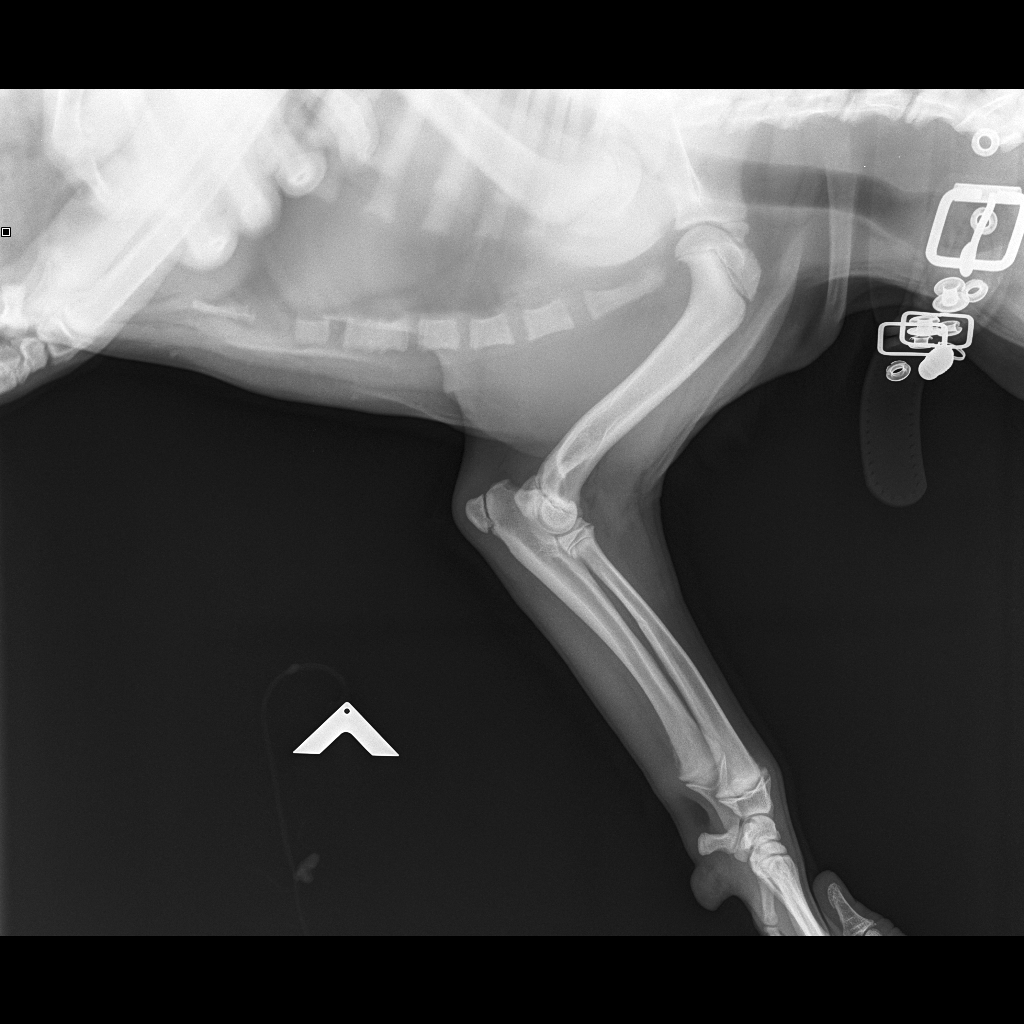

Рентгеновские снимки перелома лапы у кота: диагностика и лечение